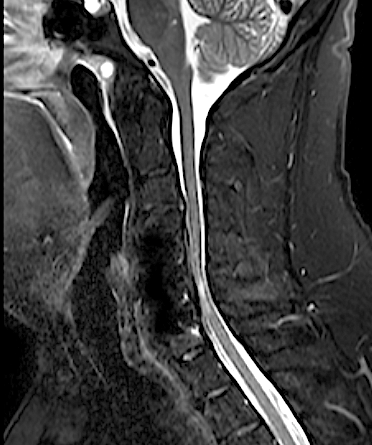

El paciente presentó a las 24horas un agravamiento de la paresia C7 derecha indolora, sin cambios en el puntaje (EMS) de su mielopatía, por lo que se decidió realizar una RM cervical urgente.

El resultado de la RM cervical planteaba dudas si era necesario o mandatorio realizar una descompresión posterior complementaria. Sin embargo, los parámetros clínicos no sugerían una compresión medular: la evolución lenta a la mejoría de su paresia, la ausencia de progresión de su mielopatía y la ausencia de dolor resultaron determinantes para que se adoptara una actitud conservadora. El paciente fue dado de alta (en plena pandemia de covid) y la evolución fue buena a pesar de que no pudo completar la rehabilitación. Se realizó nueva RM y RX cervical a los seis meses que resultó mucho más concluyente.

RM postoperatorio